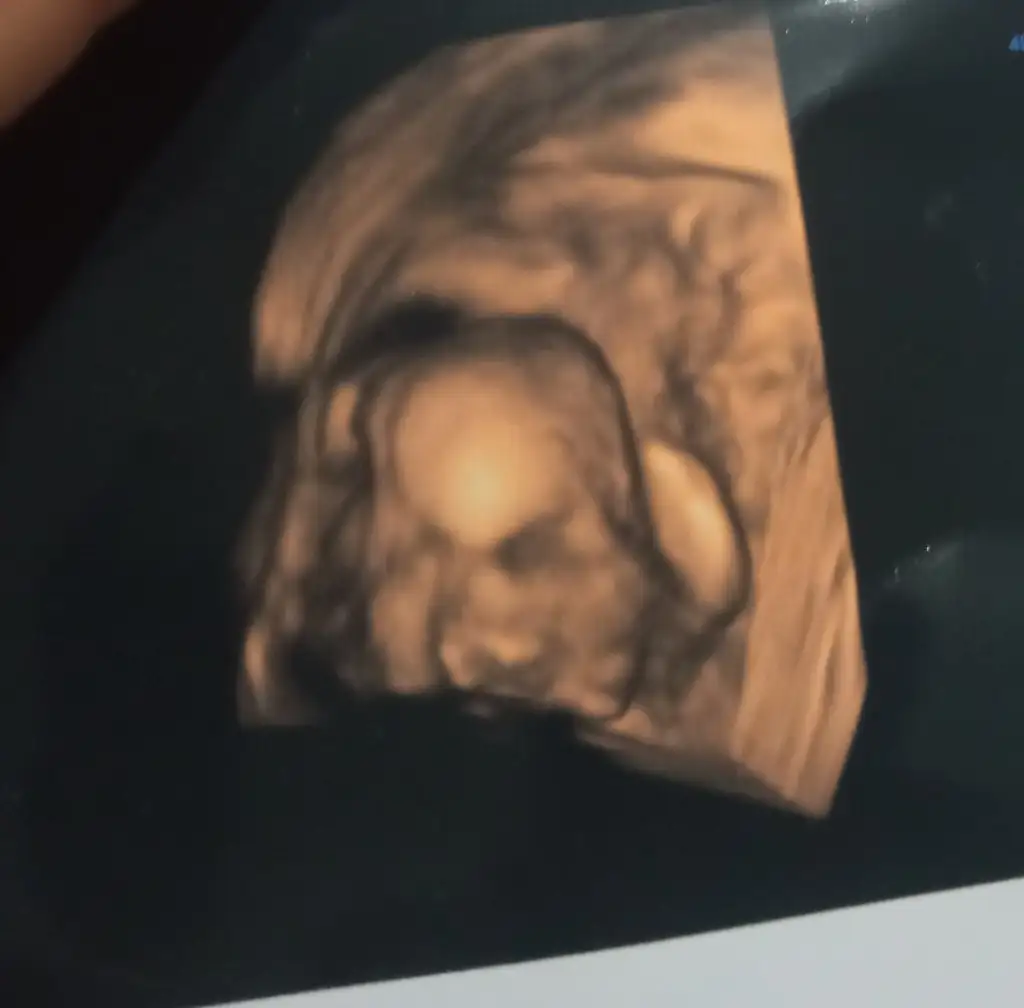

Benim kasıklarımda ağrı oluyor ve çok akıntım var pek doktora gitmiyorum bu gün gitim ve ama akıntım olduğunu söyleyemedim ben evlilik dışı hamile kaldım ve bu gün bir oğlum olacağını da öğrendim net bir şekilde ve ben hareketlerini hissetmiyorum pek normalmı bide bebek niyw böyle normalmı teşekkür ederim

• IMG_20220111_063332.webp